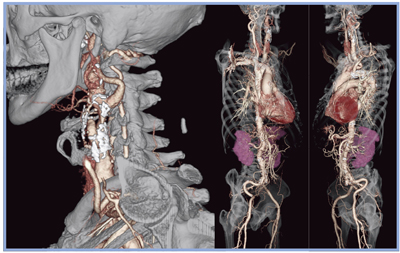

図1は,当直時間帯に脳外科から依頼され,全身の血管撮影(CTA)を行った症例である。Aquilion PRIMEはスキャン時間10秒以内で,末梢血管に至るまで鮮明なボリュームレンダリング(VR)画像を得ることができる。

図1 当直時間帯に行われた検査のVR画像(左頸動脈狭窄症例)

120kV,Volume EC(20〜62mAs),0.35s/rot,0.5mm×80,HP65(0.81),AIDR 3D(Standard)9.8s